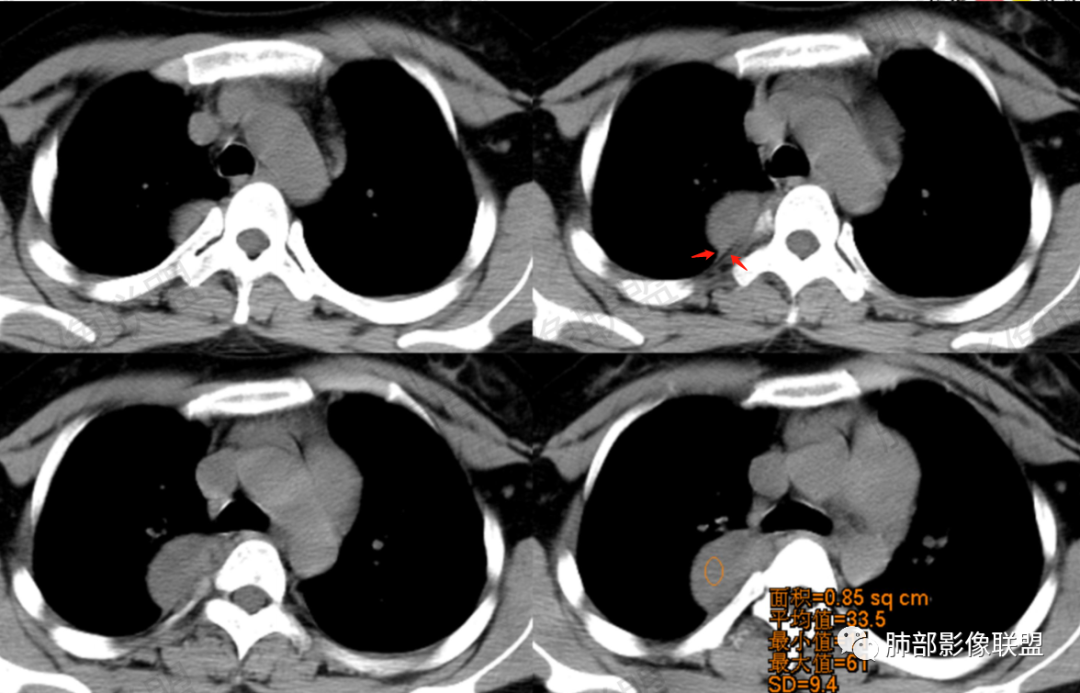

CT值平扫33HU,增强:45HU左右

2.右后纵隔脊柱旁上下方向贴伏块影,“肾”形外观,边界清晰,密度不均,中央区域见脂肪密度影引向椎体前方,未见液性密度管腔影及钙化。

3.块影血供动脉来自肋间动脉,且由内后方侧入,其与下腔静脉之间未见回流通道。血管未见破坏,相邻组织未见侵入。

4.块影未延伸至椎管内,未见椎间孔扩大或骨质吸收破坏。

5.轻度渐进性强化。